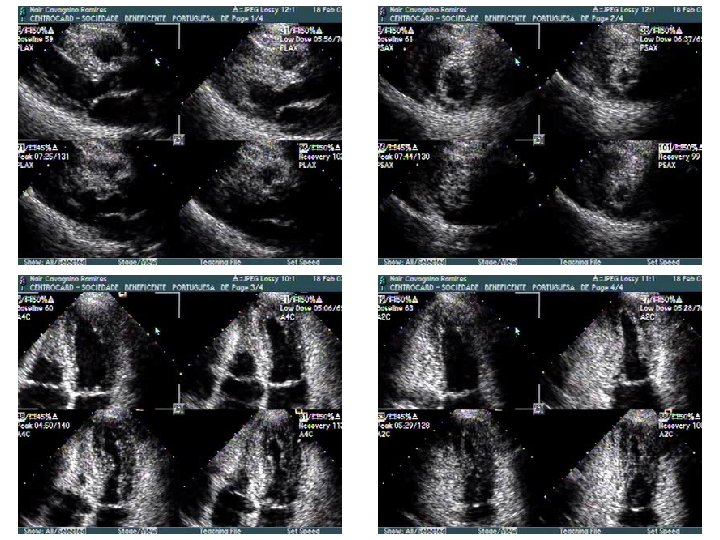

Repouso 4 c diástole Dipiridamol 4 c 2 c diástole 4 c sístole 2 c sístole

r e p o u s o 4 c diastole 2 c diastole 4 c sístole 2 c sístole D I P t o t al antes cirurgia 30 dias cirurgia 4 c diastole 2 c sístole